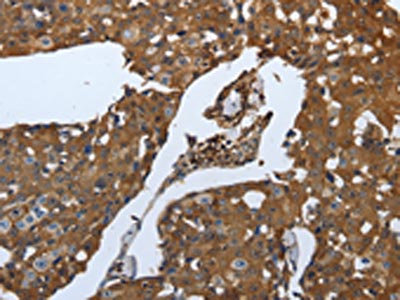

The image on the left is immunohistochemistry of paraffin-embedded Human breast cancer tissue using CSB-PA140842(SLC34A2 Antibody) at dilution 1/70, on the right is treated with synthetic peptide. (Original magnification: ×200)

The image on the left is immunohistochemistry of paraffin-embedded Human ovarian cancer tissue using CSB-PA140842(SLC34A2 Antibody) at dilution 1/70, on the right is treated with synthetic peptide. (Original magnification: ×200)